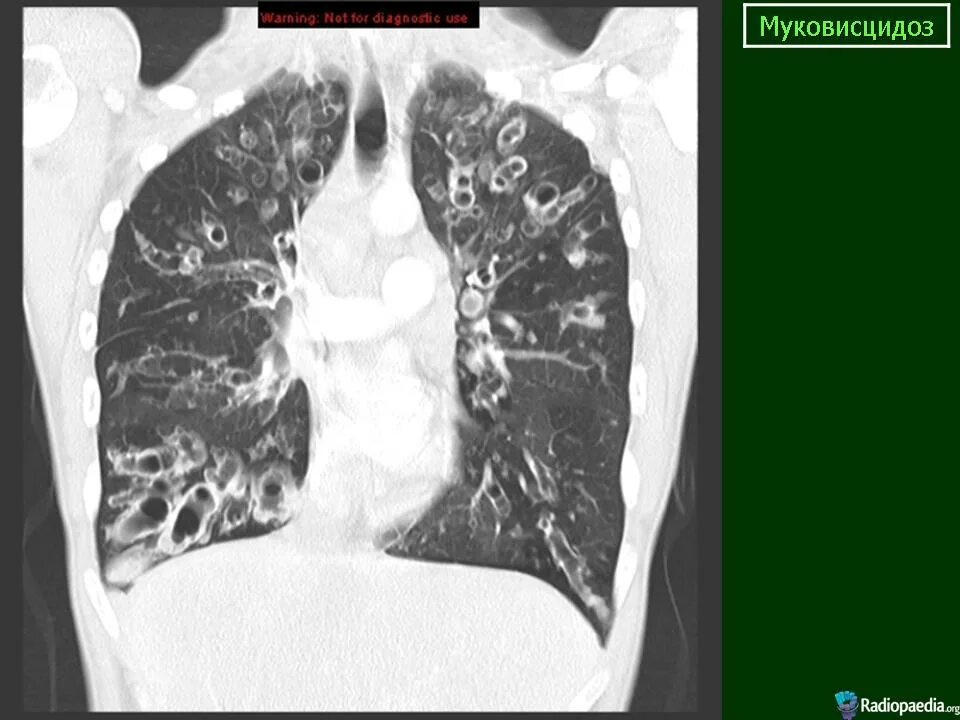

Фиброз кт